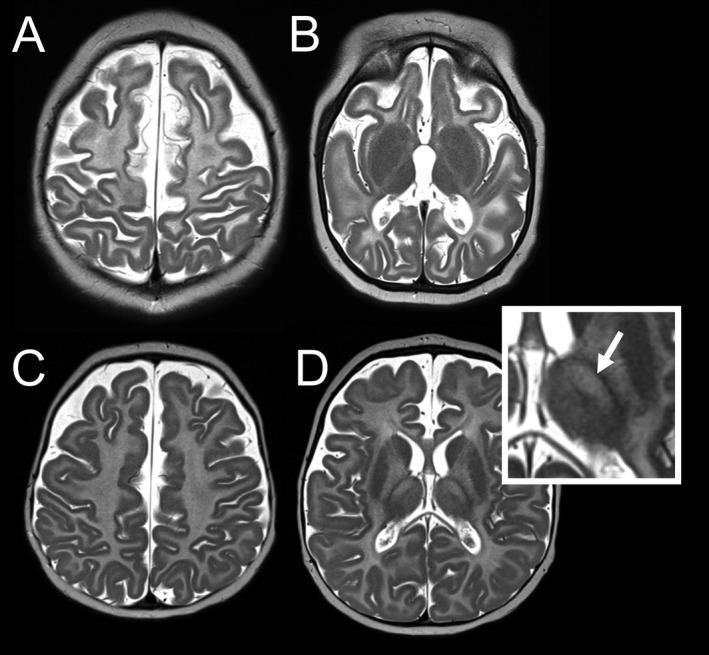

Biallelic variants in RARS1, encoding the cytoplasmic tRNA synthetase for arginine (ArgRS), cause a hypomyelinating leukodystrophy. This study aimed to investigate clinical, neuroradiological and genetic features of patients with RARS1-related disease, and to identify possible genotype-phenotype relationships.

We performed a multinational cross-sectional survey among 20 patients with biallelic RARS1 variants identified by next-generation sequencing techniques. Clinical data, brain MRI findings and genetic results were analyzed. Additionally, ArgRS activity was measured in fibroblasts of four patients, and translation of long and short ArgRS isoforms was quantified by western blot.

Clinical presentation ranged from severe (onset in the first 3 months, usually with refractory epilepsy and early brain atrophy), to intermediate (onset in the first year with nystagmus and spasticity), and mild (onset around or after 12 months with minimal cognitive impairment and preserved independent walking). The most frequent RARS1 variant, c.5A>G, led to mild or intermediate phenotypes, whereas truncating variants and variants affecting amino acids close to the ArgRS active centre led to severe phenotypes. ArgRS activity was significantly reduced in three patients with intermediate and severe phenotypes; in a fourth patient with intermediate to severe presentation, we measured normal ArgRS activity, but found translation mainly of the short instead of the long ArgRS isoform.

Variants in RARS1 impair ArgRS activity and do not only lead to a classic hypomyelination presentation with nystagmus and spasticity, but to a wide spectrum, ranging from severe, early-onset epileptic encephalopathy with brain atrophy to mild disease with relatively preserved myelination.